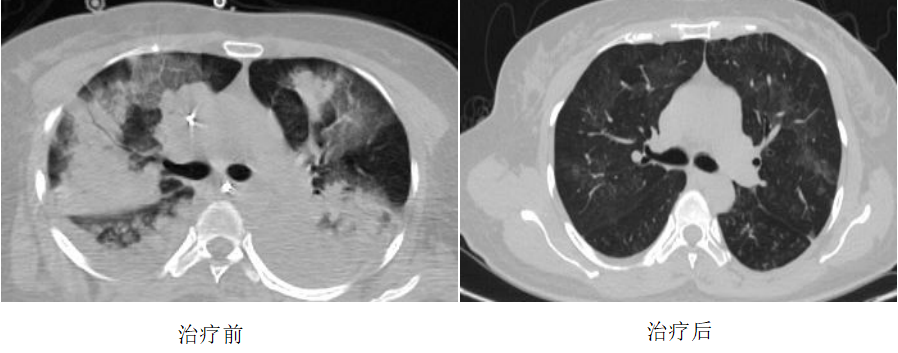

此时,患者生命垂危,医护团队立即采取抗感染、肺保护性机械通气、镇静镇痛、纤支镜、抗炎、俯卧位通气等一系列治疗措施。然而,患者病情未见缓解,血压和氧合难以维持,在呼吸机纯氧模式下,氧饱和度仅能维持在80%左右。CT显示双肺已呈“白肺”,随时可能出现心跳、呼吸骤停,生命危在旦夕。

经过7天的ECMO及综合救治,患者肺部功能明显改善,成功撤离ECMO。2天后,患者顺利脱机拔管。当患者说出“好喘多了”时,医护人员的所有努力都得到了回报。4月1日,患者从重症医学科转回呼吸与危重症医学科二病区,并于4月8日康复出院。